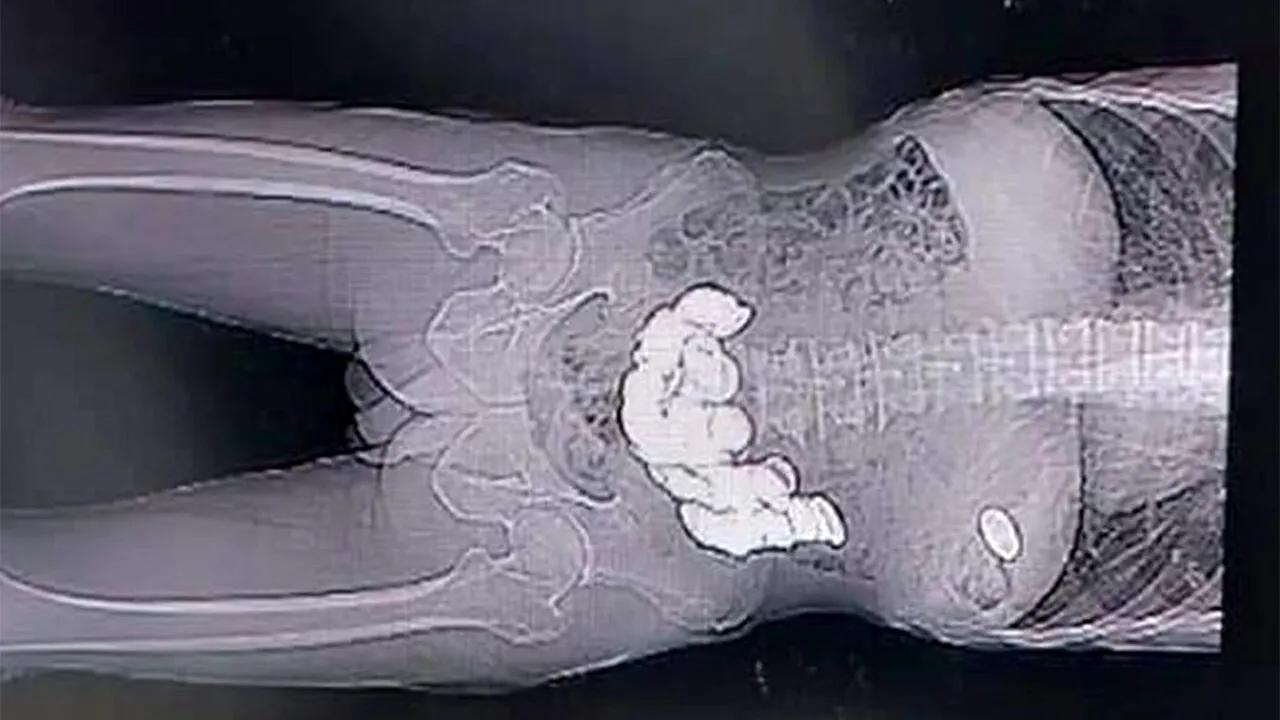

După examinare, doctorii de la Spitalul Hangal Sri Kumareshwar au descoperit în stomacul acestuia peste 1,5 kilograme de monede.

„Suferea de o problemă psihiatrică. A înghițit aceste monede în ultimele două-trei luni. A venit la spital plângându-se de vărsături și disconfort abdominal. Pe baza simptomelor lui, am făcut o radiografie și o endoscopie și am găsit monede în stomac.

Așa că, am decis să-l operam urgent. Stomacul a fost dilatat enorm. O mulțime de monede au fost blocate în diferite locuri ale stomacului”, a declarat medicul Kalaburgi, potrivit Dailystar.com.